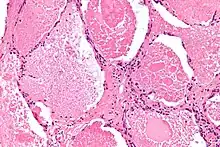

Micrograph of pulmonary alveolar proteinosis, showing the characteristic airspace filling with focally dense globs referred to as chatter or dense bodies. H&E stain. | |

Lung washings or tissue for histopathologic analysis are most commonly obtained using bronchoalveolar lavage and/or lung biopsy.[12] Characteristic biopsy findings show filling of the alveoli (and sometimes terminal bronchioles) with an amorphous eosinophilic material, which stains strongly positive on PAS stain and the PAS diastase stain. The surrounding alveoli and pulmonary interstitium remain relatively normal.[13] Electron microscopy of the sample, although not typically performed due to impracticality, shows lamellated bodies representing surfactant.[14] An alternative diagnosis with similar histomorphologic findings is Pneumocystis jirovicii pneumonia.[14]

Lung washings characteristically yield a fluid which is "milky"composition. Under the microscope, samples show 20-50 micrometer PAS-positive globules on a background of finely granular or amorphous PAS-positive material. There is typically a low numbers of macrophages and inflammatory cells (although this is variable).[13][14]